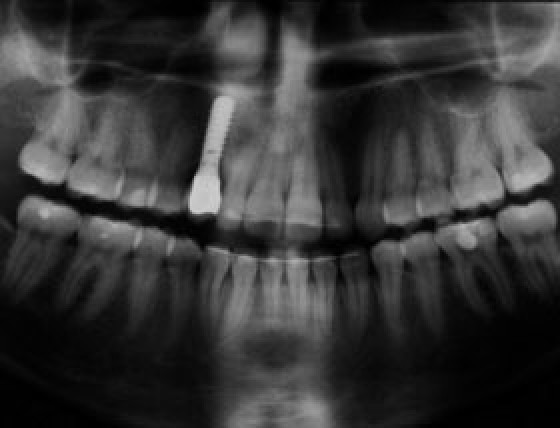

ivoris® express ceph

FRS-Analysevorschläge* in unter einer Sekunde.

Die KI in ivoris® express ceph wurde auf Basis tausender manueller Auswertungen trainiert und mit der Expertise erfahrener Kieferorthopäd:innen entwickelt. So unterstützt sie Zahnärztinnen und Zahnärzte sowie KFOs effizient bei der Befundung – mit präzisen, sofort verfügbaren Ergebnissen.

Ihre Vorteile mit ivoris® express ceph:

- Automatische FRS-Auswertungen in < 1 Sekunde

- KI-gestützt mit Schädel- und Weichteilstrukturen

- Trainiert auf tausenden manuellen Analysen von KFO-Expert:innen

- Präzise Unterstützung bei Befundung und Planung

- Zehn kostenfreie Testauswertungen inklusive

* Alle Auswertungen des Moduls sind Analysevorschläge, die der medizinischen Kontrolle der verantwortlichen Zahnärzte unterliegen.

Schneller befunden. Sicher entscheiden.

Fordern Sie Ihr persönliches Angebot für ivoris® express ceph an und testen Sie die KI-gestützte FRS-Analyse mit zehn kostenfreien Auswertungen.

ivoris® express ceph – Jetzt aktivieren.

Mit Absenden des Formulars bestätigen Sie, dass Sie das Modul express ceph zu 35,- € mtl. zzgl. MwSt. bestellen.

Für die Freischaltung von Modulen kann zusätzlich eine Servicepauschale mit 35,- € je 15 Minuten berechnet werden.